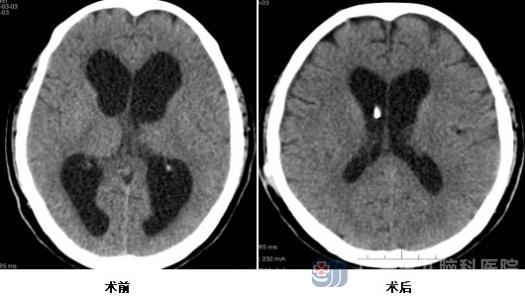

在一筹莫展之际,患者家属了解到广东三九脑科医院神经外十科在处理术后感染等神经外科并发症方面拥有丰富经验和突出实力,随即慕名找到神经外十科欧阳辉教授,并将患者转院至此。入院后,外十科第一时间为患者开展全面细致的检查,确诊其为颈椎术后切口感染伴持续渗液,且感染导致患者脑积水严重,脑室增大,病情复杂且危急。

治疗初期,神经外十科医护团队精准选用抗生素,个性化护理等措施,严格把控感染指标,逐步将炎症控制在安全范围,防止并发症的发生。待感染得到有效遏制后,团队先后为患者实施多次手术:首次手术重点缓解患者脑积水症状,降低颅内压同时积极抗感染治疗;后续手术则是完成颈部硬脊膜漏修补术等关键环节,每一次手术都精准操作、层层推进,最大程度降低手术风险,保障修复效果。